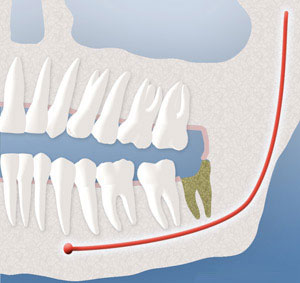

Sinus Communication:

The upper wisdom teeth are situated close to your sinuses, and their removal can result in an opening between your mouth and the sinus. Once again, if the teeth are removed at an early age, the root formation is minimal, and this complication is very unlikely. However, if it does occur, it will usually close spontaneously, but we may give you special instructions to follow, such as avoiding blowing your nose for about two weeks following the surgery. You can wipe your nose, but don’t blow your nose. If you have to sneeze, you should sneeze with an open mouth into a tissue. Pressure should not be created in the sinus area, which may dislodge the healing blood clot. If you sense this condition occurring after the surgery, please contact our office. An additional procedure may rarely be necessary to close the opening.